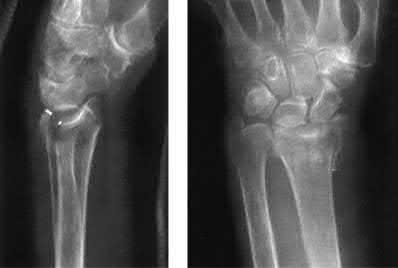

A 12-year-old male sustains an ulnar fracture with an associated posterior-lateral radial head dislocation. After undergoing closed reduction, the radiocapitellar joint is noted to remain non-concentric. What is the most likely finding?

In pediatric Monteggia fractures the annular ligament is commonly interposed in the radiocapitellar joint.

Bado initially described and classified Monteggia fractures. The most common injury pattern is an extension type 1 with anterior radial head dislocation and apex anterior ulnar shaft fracture. The apex of the ulna fracture determines the direction of the radial head subluxation or dislocation. Adults typically require ORIF of the ulna. These fractures in children are often treated non-operatively with closed reduction if the ulna fracture is transverse and stable. Type III is the one most commonly associated with irreducibility of the radial head because of interposition of the annular ligament. The incidence of posterior interosseous nerve injury is high with this lesion. The nerve deficit usually completely resolves rapidly and spontaneously.

Tan et al reviewed their treatment of 35 children with Type I and Type III Monteggia fractures. All radial heads were explored and the interposed annular ligament was stretched out of the joint space. They noted that none of the patients had any recurrent dislocation or subluxation.

Ring et al in their review stress the importance of an anatomic reduction of the ulna to restore the reduction of the radial head.